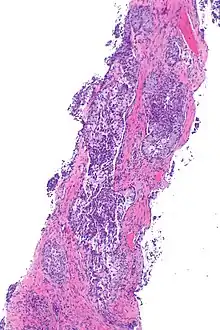

Micrograph showing ALK positive lung adenocarcinoma. H&E stain.

Most lung carcinomas containing the ALK gene fusion are adenocarcinomas.

Some studies suggest that the papillary adenocarcinoma and the signet ring cell adenocarcinoma[5] variants are more likely to carry this fused gene than other histological variants.